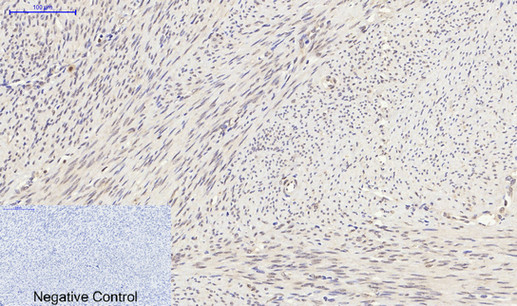

- Scientific DescriptionRabbit polyclonal antibody to Synapsin.